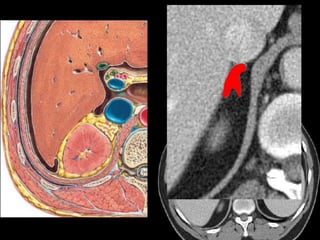

Liver:

 Lies mostly in the

right

hypochondrium, and

protected by rib

cage.

 Divided into two

lobes of unequal size

by the falciform

ligament.

3/22/2024 17

Gallbladder :

 lies in a fossa on the visceral surface of the liver to the right of

the quadrate lobe.

 It stores and concentrates bile, which enters and leaves through

the cystic duct. The cystic duct joins the common hepatic duct

to form the common bile duct.

3/22/2024 27